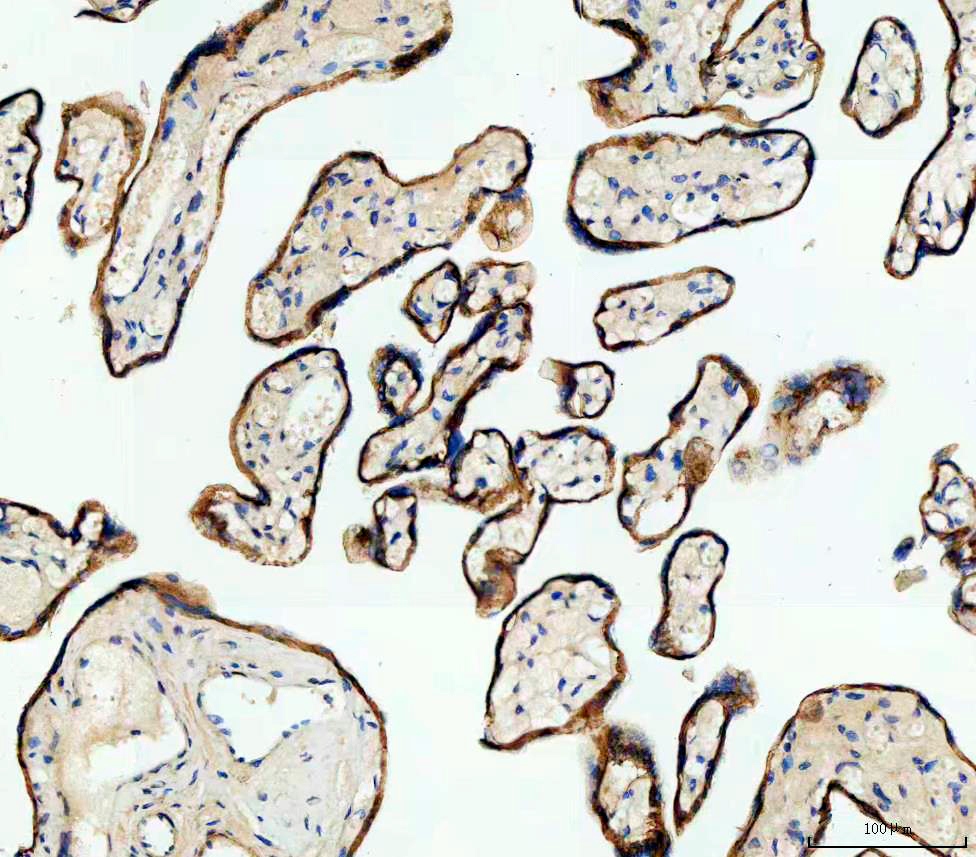

IHC analysis of E-cadherin/CDH1 using anti-E-cadherin/CDH1 antibody (PB9561).

E-cadherin/CDH1 was detected in a paraffin-embedded section of human placenta tissue. The tissue section was incubated with rabbit anti-E-cadherin/CDH1 Antibody (PB9561) at a dilution of 1:200 and developed using HRP Conjugated Rabbit IgG Super Vision Assay Kit (Catalog # SV0002) with DAB (Catalog # AR1027) as the chromogen.